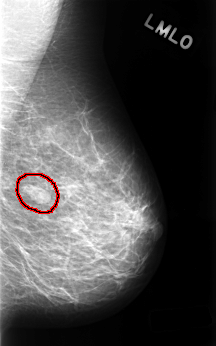

C_0489_1.LEFT_MLO

LEFT_MLO LINES 4488 PIXELS_PER_LINE 2800 BITS_PER_PIXEL 12 RESOLUTION 50 OVERLAY

FILE: C_0489_1.LEFT_MLO.OVERLAY

TOTAL_ABNORMALITIES 1

ABNORMALITY 1

LESION_TYPE MASS SHAPE OVAL MARGINS CIRCUMSCRIBED

ASSESSMENT 3

SUBTLETY 5

PATHOLOGY BENIGN

TOTAL_OUTLINES 1

BOUNDARY